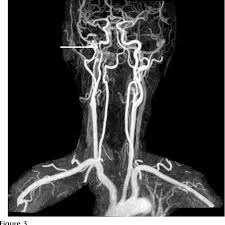

Scad most commonly affects women in their 40s and 50s. Dissection of the vertebral artery occurs in 1 per 100,000 of the population, however it makes up about 25% of all cerebral events in those less than 40 year of age (2). Approximately 2.5% of all strokes in the u.s. A carotid dissection is a tear in the artery wall that allows blood to flow between the wall layers. It is mainly characterised by local signs such as headache. A carotid dissection can be due to injury. These are a set of paired arteries at the sides of your neck. Carotid dissection is about 3 times commoner than vertebral. It can be due to injury. Spontaneous dissection of the carotid artery occurs in 3 per 100,000 of the population annually (1). Carotid artery dissection is a tear in one of the layers of the artery wall. Soldiers often engage in leisure, training, and combat activities that place them at risk for sustaining an injury that causes a carotid artery dissection. If a diagnosis of spontaneous internal carotid artery dissection is under consideration, laboratory studies are largely irrelevant for diagnostic purposes.

Carotid artery dissection is a tear in one of the layers of the artery wall. Spontaneous dissection of the carotid artery occurs in 3 per 100,000 of the population annually (1). The natural history of cerebrovascular fmd is unknown and management of symptomatic patients can be challenging. Blood vessel walls normally have three layers, and a tear in any of these can allow blood to flow into the resulting space, causing the vessel to bulge. Carotid artery dissection is a major cause of cerebral infarction in the young. Carotid artery dissection has been described after chiropractic manipulation. May occur spontaneously, or in the setting of major/minor neck trauma (mvc (classically a seat belt injury)) vs. Scad can slow or block blood flow to the heart, causing a heart attack, abnormalities in heart rhythm or sudden death.

Arterial dissection is a tear of the inside of the artery. The tear that initiates the dissection may occur spontaneously or after injury. Medical imaging tests can help rule out other conditions with similar symptoms. The first portion of each carotid artery is the called the common carotid artery. These arteries supply blood to your brain. May occur spontaneously, or in the setting of major/minor neck trauma (mvc (classically a seat belt injury)) vs. Similarly, dissections affect distal parts of the extracranial vertebral artery, whereas atherosclerosis tends to involve the proximal segments C0338585) spontaneous or traumatic separation of the layers of the carotid artery wall. Carotid dissection is a tear in the carotid artery wall. But it's still a dangerous situation. I will elaborate in a few sentences. Blood vessel walls normally have three layers, and a tear in any of these can allow blood to flow into the resulting space, causing the vessel to bulge. It manifests with headache, neck pain, temporary vision loss, and/or ischemic stroke.